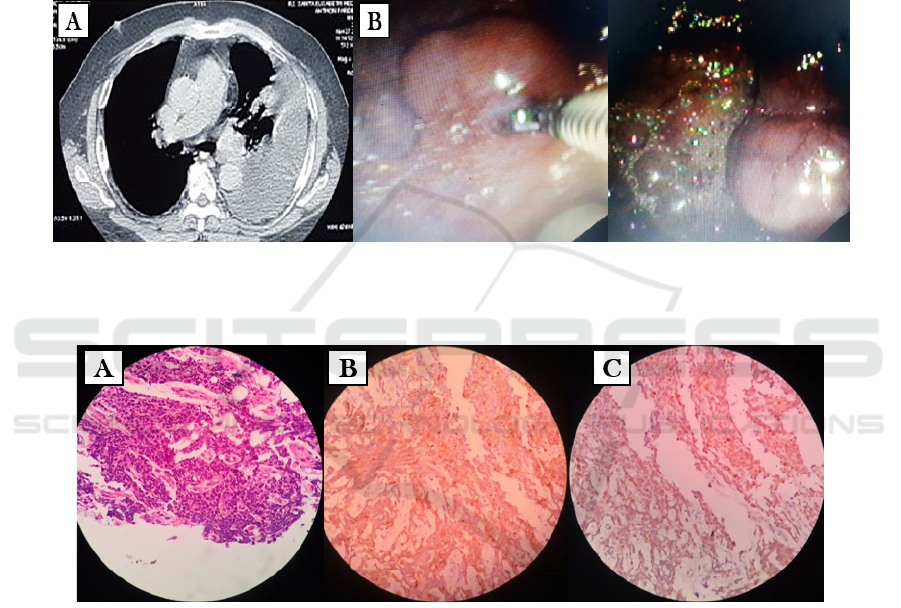

inflammatory smear. Thoracic CT scan revealed a

suspicion for left pleural tumors in the apex and

medial to lower field along with massive left pleural

effusion and left inferior lobe atelectasis (Figure

1A).

Pleuroscopy was then performed and multiple

masses in the parietal pleura and visceral pleura

were found, continued with biopsy (Figure 1B).

Histopathologic finding supported the diagnosis of

mesothelioma (Figure 2A). Immunohistochemistry

examination with Pancytokeratin, EMA (Figure 2B)

and calretinin (Figure 2C) were conducted with

positive result, confirming the diagnosis of stage

IIIB malignant pleural mesothelioma. He was then

Figure 1: (A) Thoracic CT scan revealed a suspicion for left pleural tumors in the apex and medial to lower field along with

massive left pleural effusion and left inferior lobe atelectasis. (B) Multiple masses in the parietal pleura and visceral pleura

were found.

Figure 2: (A) Histopathologic finding supported the diagnosis of mesothelioma, Immunohistochemistry examination with

Pancytokeratin, EMA. (B) and calretinin. (C) were conducted with positive result, confirming the diagnosis of malignant

pleural mesothelioma.